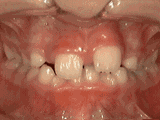

Crowded teeth, certain teeth in abnormal positions, and narrow dental arch result in localized tooth overlap. After extracting one tooth on each side and undergoing orthodontic treatment, the result can be as follows: